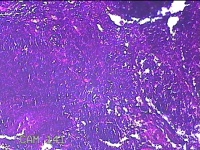

性别

女

年龄

6岁

临床诊断

1.阻塞性睡眠呼吸暂停综合征 2.腺样体肥大 3.扁桃体肥大 4.变应性鼻炎

一般病史

鼻塞、张口呼吸伴睡眠呼吸暂停半年余。

标本名称

双侧扁桃体

大体所见

灰白粉红色扁桃体4x3x0.8cm两个,表面均有部分糜烂,切面灰白粉红色,结节状,质软。